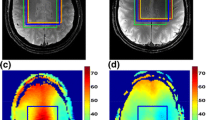

Figure 1 shows one slice of the 1H maps and 23Na images from the 3 scans of subject 1 after co-registration and masking. Figure 2 shows one selected slice of the 1H maps and 23Na images from the first scan of each subject after co-registration, using the maps from the subject 1 as a reference, and masking. Figure 3 shows the brain segmentation in gray matter (GM), white matter (WM), and cerebrospinal fluid (CSF) of scan 1 for subject 1. Table 1 summarizes the results of the statistical analysis for all tissues and all scans, where Meanall and SDall are the mean value and standard deviation calculated over all the data, Inter-Var is the inter-subject variation, Intra-Var is the mean intra-subject variation, CV is the mean coefficient of variation and ICC is the intra-class variation. Figure 1S in supplementary information shows images from subject 2 along the 3 axes.

Maps from the first scan acquired in all the subjects (after co-registration, using subject 1 as reference) with simultaneous 1H MRF/23Na MRI. The in-plane resolution is 1.5 × 1.5 mm2 for the proton images and 2.85 × 2.85 mm2 for the sodium image. Slice thickness is 3 mm for both nuclei. PD is normalized proton density and 23Na D is normalized sodium density.

The 3D simultaneous 1H MRF/23Na MRI sequence parameters were: FOV 240 × 240 × 168 mm3, 1H 160 × 160/23Na 84 × 84 matrix, 1H 1.5 × 1.5 mm2/23Na 2.85 × 2.85 mm2 in-plane resolution, 1H TR = 7.5 ms/23Na TR = 15 ms, 1H TE = 2 ms/23Na TE = 1 ms, 1 slab of 56 slices, 3 mm slice thickness for both 1H and 23Na, 6 shots per slab, total scan time 21 min.

In order to realize a quantitative analysis, we normalized the proton and sodium density-weighted images. The PD map was normalized by the mean intensity of the CSF measured over the pixels of the CSF binarized mask to minimize partial volume effects (as described previously). The 23Na density-weighted was normalized by the mean sodium intensity in the eyes (vitreous humor), which exhibited the maximum signal intensity in the sodium images. A manual ROI over the whole image volume that contains only the eyes was applied to calculate the mean eye intensity. The final sodium density-weighted image is therefore a normalized sodium density-weighted image that is proportional to some extent to the TSC. Nevertheless, this image should not be confounded with a TSC map since the effect of sodium relaxation times in different tissues were not measured nor mitigated by the acquisition (TE = 1 ms, TR = 15 ms, FA = 30°) in this case.